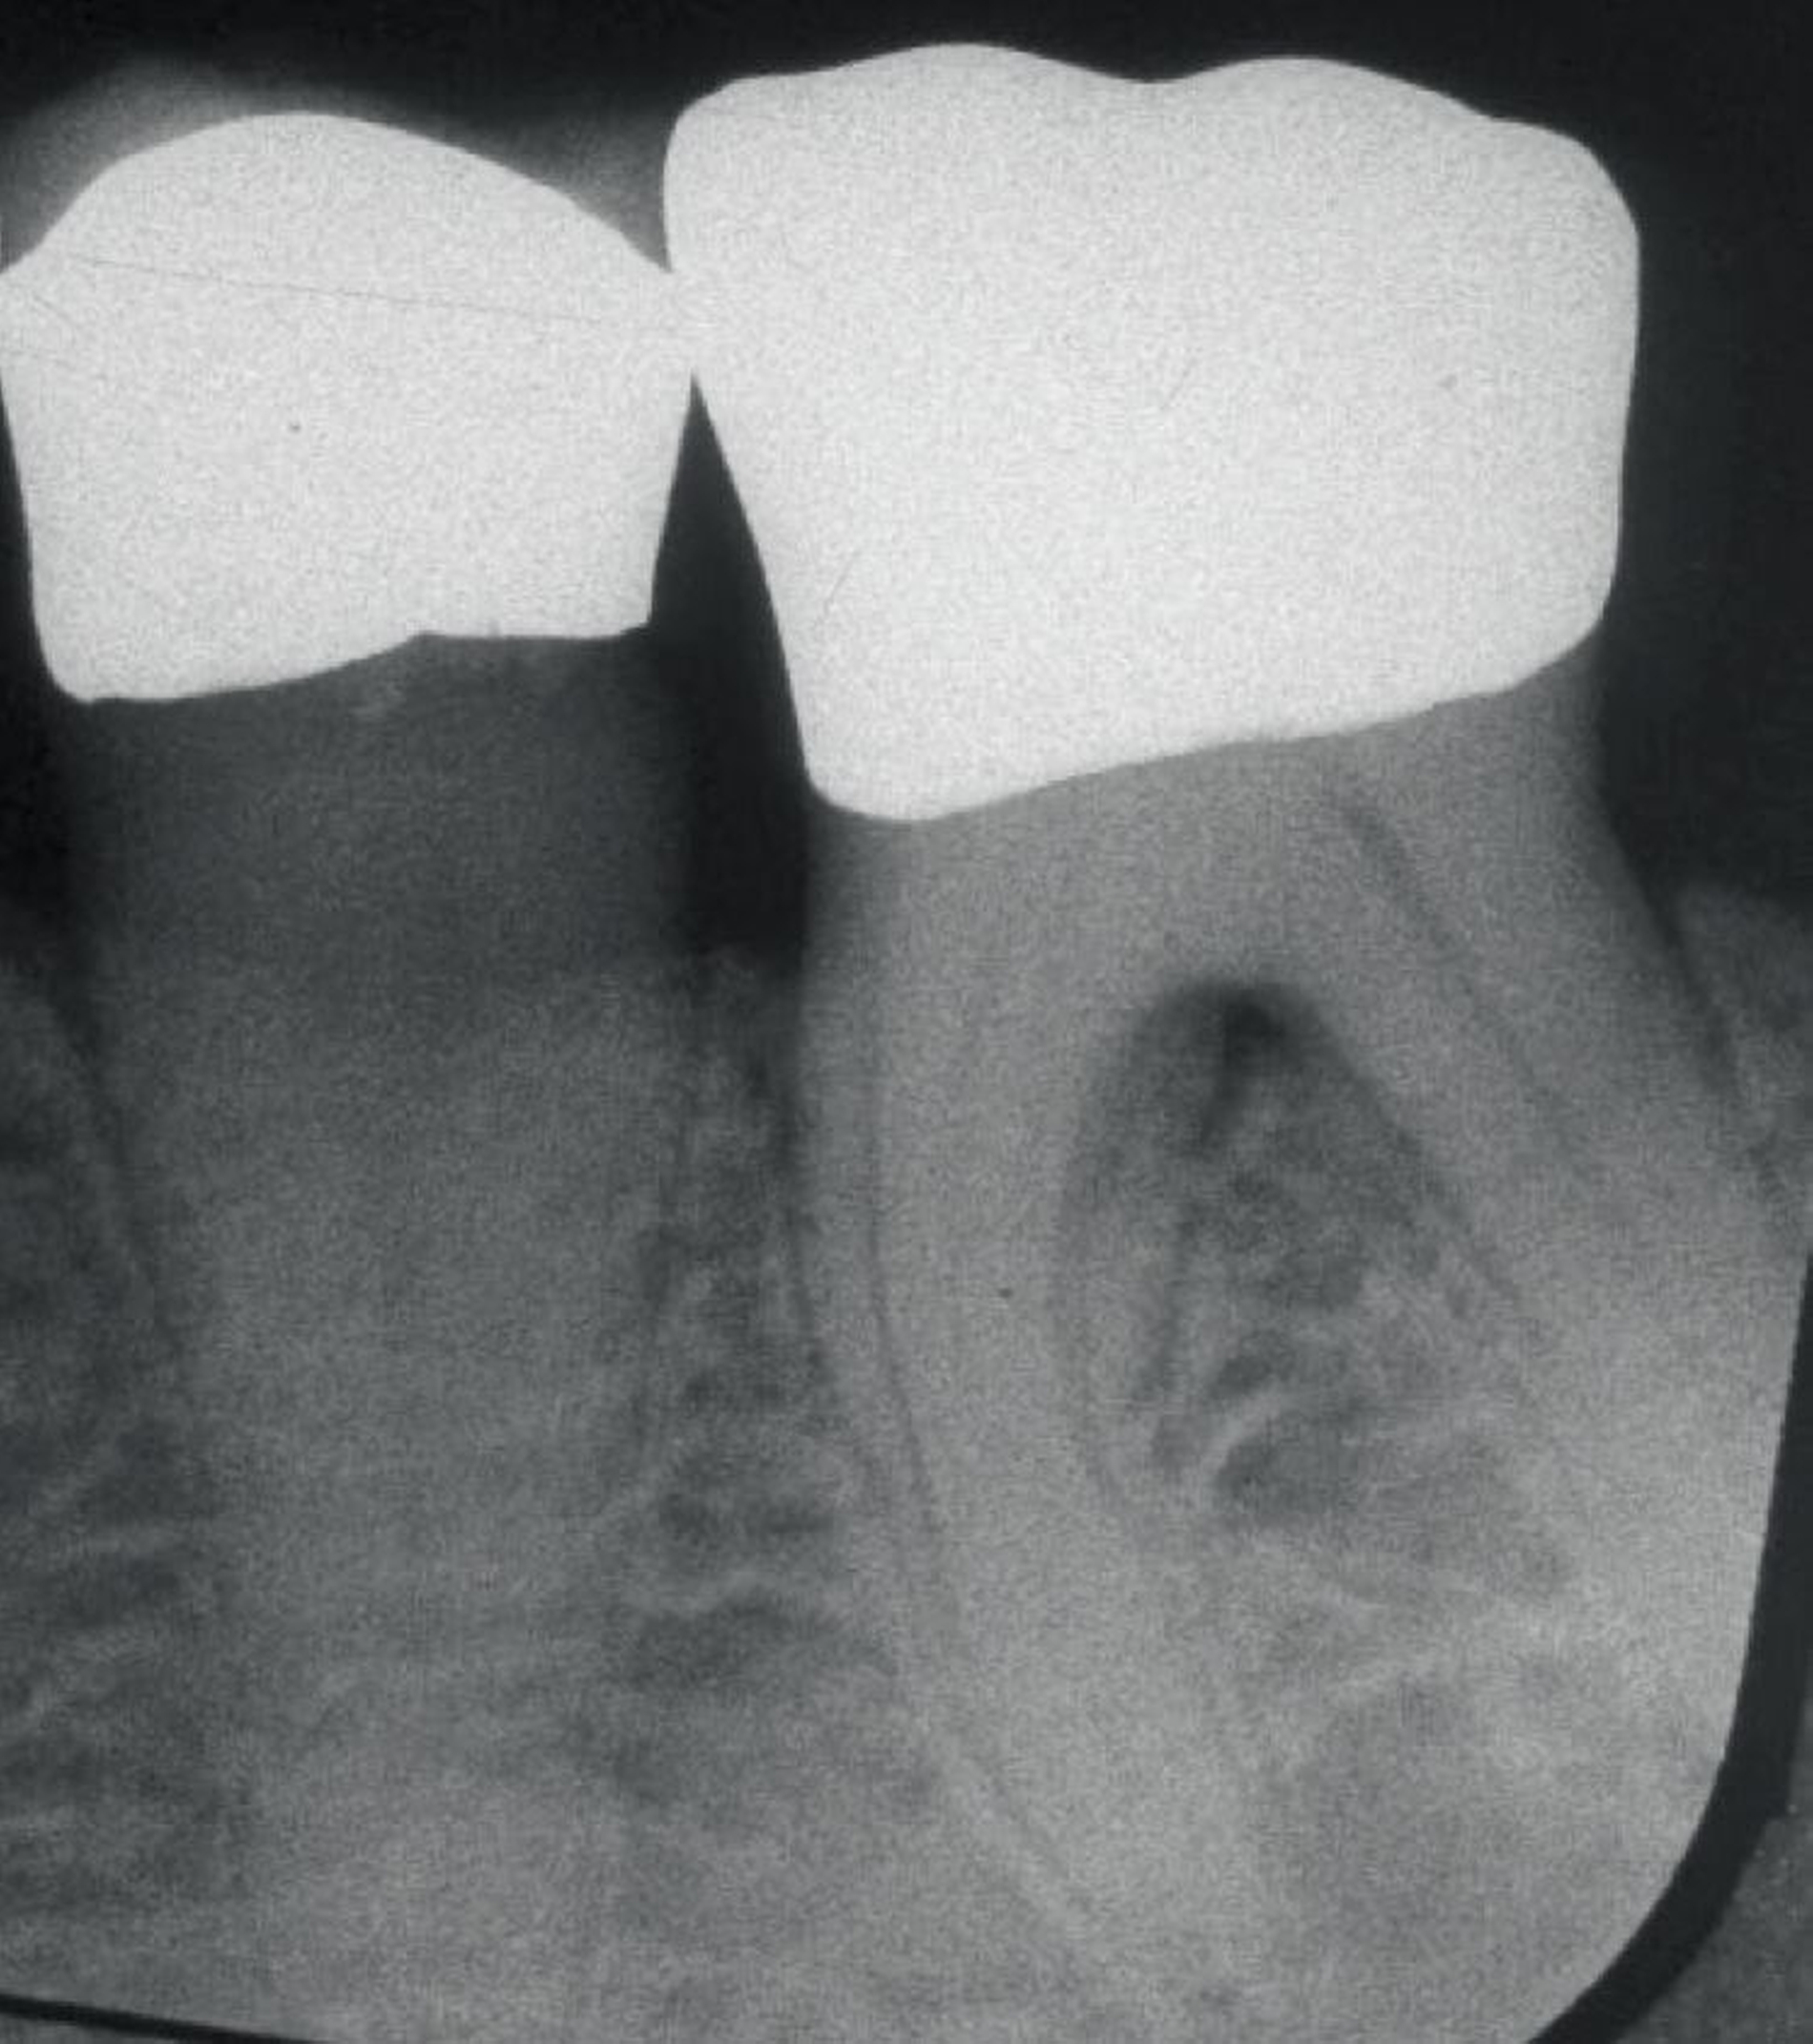

Da der histologische Nachweis einer erfolgreichen Furkationsregeneration kein praktikabler Endpunkt für kontrollierte klinische Studien ist, dienen Veränderungen bei direkten Knochenmessungen (offene Messungen: horizontales Knochensondierungsniveau bei der Operation und während eines „Re-entry“-Eingriffs) als primäre Ergebnisvariablen zur Bewertung des klinischen Erfolgs, während geschlossene Messungen wie der klinische Attachmentgewinn (horizontales/vertikales Attachmentniveau (CAL)), die Reduktion der Taschensondierungstiefe (TST) und röntgenologische Beurteilungen als sekundäre Zielparameter dienen können [Machtei, 1997]. Zu den von den Patienten berichteten Ergebnissen nach einer regenerativen Furkationschirurgie können postoperative Schmerzen, die Komplikationsrate, der wahrgenommene Nutzen und die Veränderung der Lebensqualität gehören.

Ein adäquater Zugang zum Operationsbereich und auch für die zukünftigen Mundhygienemaßnahmen ist äußerst wichtig. Molaren mit Grad-II-Furkationsdefekten (mandibulär und bukkal maxillär) sind Kandidaten, die für ein regeneratives Verfahren infrage kommen. Basierend auf der verfügbaren Evidenz sind interdentale Grad-II-Furkationsdefekte an Oberkiefermolaren deutlich weniger geeignet, höchstwahrscheinlich aufgrund des eingeschränkten Zugangs. Weitere lokale Charakteristika können Auswirkungen auf die Ergebnisse der regenerativen Furkationschirurgie haben. Zum Beispiel können ein dickerer Phänotyp und das Fehlen einer Weichgeweberezession die Heilung nach GTR-Verfahren positiv beeinflussen. Günstigere Ergebnisse sind an Stellen zu erwarten, an denen das verbleibende approximale Knochenniveau koronal zum Eingang beziehungsweise zum Dach des Furkationsdefekts liegt, verglichen mit solchen, bei denen das approximale Knochenniveau auf der Höhe oder apikal des Furkationseingangs liegt. Ein enger interradikulärer Abstand kann eine gründliche Defektinstrumentierung beeinträchtigen. Das Vorhandensein einer Wurzelkanalfüllung ist nicht per se eine Kontraindikation für die Furkationsregeneration – vorausgesetzt, es gibt keine Anzeichen für apikale pathologische Veränderungen.